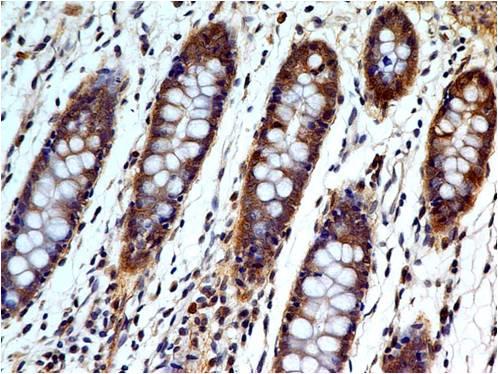

Anti-BG8 LewisY Monoclonal Antibody (Clone:IHC517)

Figure 1: Immunohistochemical analysis of BG8, Lewisy (IHC517) on Thyroid Cancer

BG8 LewisY, also known as LewisY blood antigen or simply BG8, is a blood group antigen that has been identified in many studies as a potential marker for differentiation between pulmonary adenocarcinoma (PACA) and epithelioid mesothelioma (EM). It has been reported that sensitivity of non-mesothelial antigens for adenocarcinoma is organ-dependent. When attempting to differentiate epithelioid mesothelioma from adenocarcinoma, BG8 LewisY performed at a sensitivity of 98% in the breast cancer group, and 100% in the lung cancer group.

Recommended dilutions: Immunohistochemical analysis: 1:100 - 1:200. However, this need to be optimized based on the research applications.